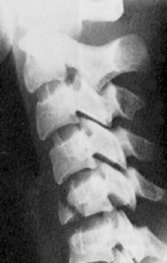

Return to Flexion Tear Drop Fracture